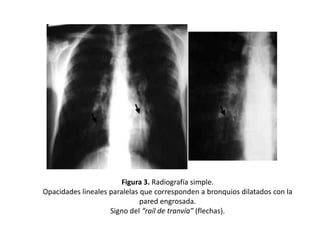

Figura 3. Radiografía simple.

Opacidades lineales paralelas que corresponden a bronquios dilatados con la

pared engrosada.

Signo del “raíl de tranvía” (flechas).

• Opacidades

lineales

paralelas

que

corresponden a bronquios dilatados con la

• Dan lugar al signo del “raíl de tranvía” (Figura

2, 3 y 4)